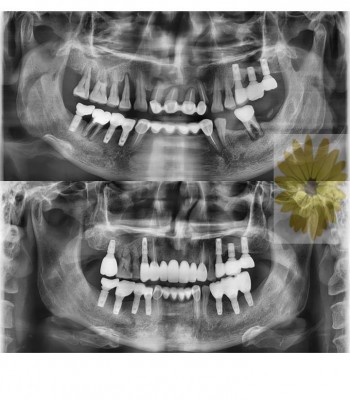

민들레치과 치료 전후사례